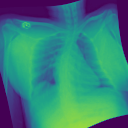

Additionally, we evaluate the performance of DiffeoNN on real-world data, using a dataset with chest X-ray images and their ground-truth lung segmentation from (RSUA, 2023). The original dataset contains images and corresponding ground-truth segmentations into three different classes (“Non-Covid”, “Covid”, and “Non-Covid-Pneumonia”). We combine the images and corresponding ground-truth segmentations of the initial three classes into one dataset, which is then split into a training dataset of image-segmentation pairs, a validation dataset of pairs, and a test dataset of pairs. We then proceed as in Section 4.1.1 to create a dataset of diffeomorphically transformed images.

We apply DiffeoNN, the inner U-Net (naïve approach) and an augmented U-Net, which is trained on the original and the diffeomorphically transformed training dataset, to the diffeomorphically transformed images from the test dataset. Visual results are presented in Figure 4 and further details on the experimental setup, training, and additional examples in Appendix B. The results closely mirror those obtained on the synthetic dataset, see Table 1(b). On average, DiffeoNN outperforms the naïve approach, validating the effectiveness of our approach. The canonicalisation step pushes the input image towards the training dataset by moving the thorax to a more central position and aligning the shoulders, which makes it easier for the inner U-Net to predict an accurate lung segmentation. While our method performs slightly below the augmented gold-standard baseline, it offers more flexibility by not relying on data augmentation or retraining, making it a practical and robust solution in real-world applications.

| Input | Canonicalised Input | Segmentation of | Output DiffeoNN | Output Naïve U-Net | Output Augmented U-Net | Ground-Truth Segmentation |